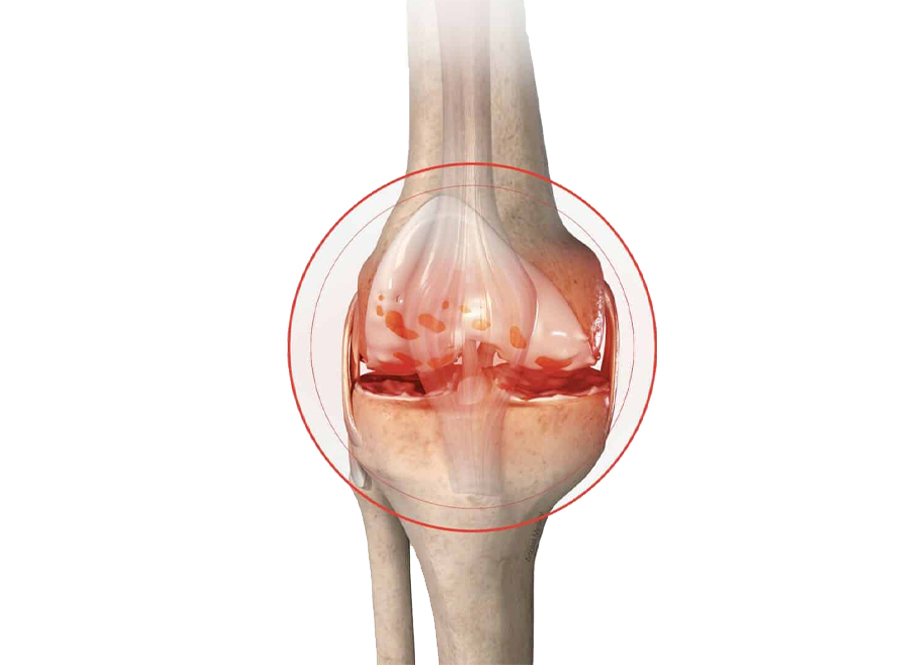

The following are the conditions that can lead to knee replacement failure and may necessitate revision surgery:

A revision knee replacement may be suggested only if non-surgical methods of symptom relief, like injections, bracing, physical therapy, or medication, do not work.